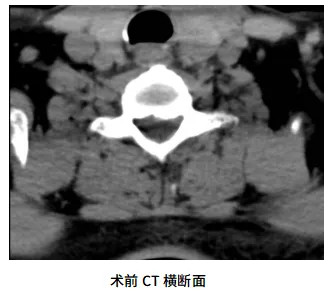

患者为七旬男性,左上肢疼痛麻木难忍3月余,以左前臂、小臂外侧为重,经过福州市多家医院的口服药物、针灸、神经阻滞等多种方式的保守治疗,患者左上肢的疼痛麻木症状始终无法解决。3个月来患者因为疼痛常常入睡困难、夜间频繁痛醒,极度影响了患者的生活。为了解决病痛,患者慕名找到了修忠标教授,期望修忠标教授团队能够为他解决痛苦,让他恢复正常生活。修教授经过详细的询问病史、体格检查、影像学分析并进行相关的鉴别诊断,确诊为:神经根型颈椎病。患者疼痛剧烈,经过3个月的保守治疗未取得明显疗效,因此治疗方案考虑行手术治疗。传统开放手术创伤大、风险相对较高,且患者高龄,抵触开放手术。基于以上的情况,修教授团队与患者及其家属深入沟通后,决定采用颈椎后路UBE技术实施微创减压手术。手术由修忠标教授亲自主刀,同麻醉科、手术室护理团队紧密配合完成。麻醉苏醒后,患者诉左上肢麻痛症状有了明显的改善。

UBE技术(单侧双通道内镜技术)通过建立两个微小通道,在清晰的内镜视野下完成复杂操作,兼具创伤小、出血少、恢复快等优势。颈椎后路UBE手术对操作精度要求极高,需在毫米级空间内完成减压。此次手术中,团队将UBE技术应用于颈椎后路,精准摘除脱出的髓核组织,彻底解除脊神经根的压迫,同时避免对周围正常结构的损伤。手术切口仅0.8cm左右,术中出血量少,术后患者症状明显缓解,次日即可下床活动 。